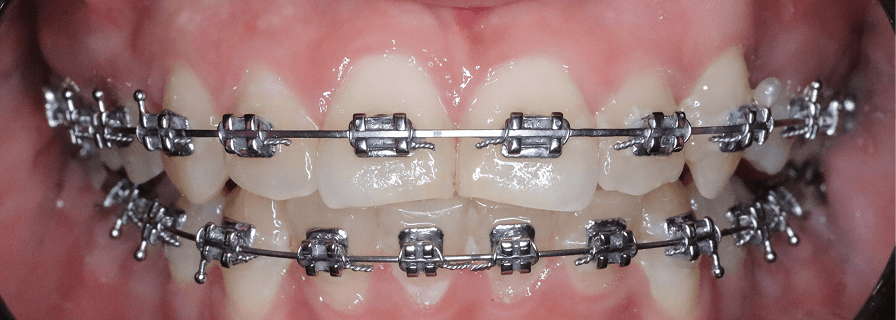

Tratament ortodontic cu disjunctor și extracții

Pacient în vârstă de 11 ani tratat cu ajutorul disjunctorului, apoi 4 extracții de premolari pentru a crea spațiu suficient erupției caninilor superiori și a permite corectarea mușcăturii.